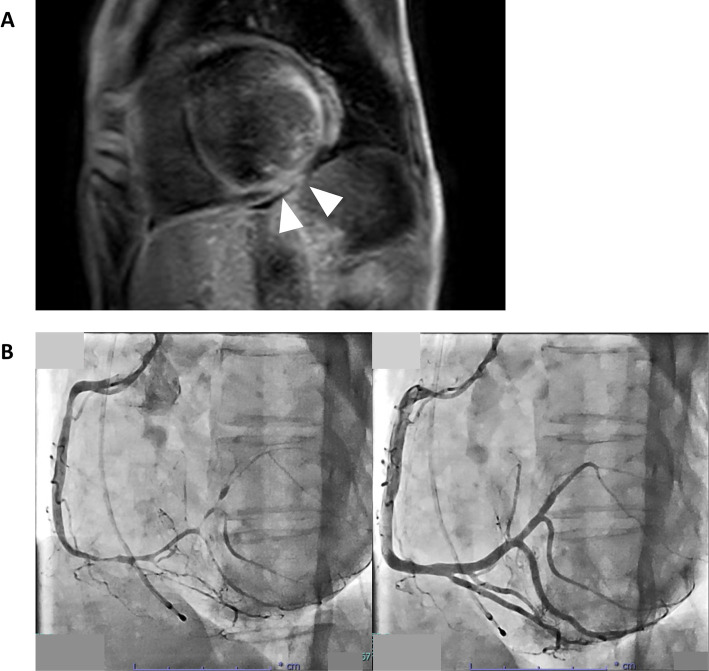

Coronary artery spasm (CAS) is an underrecognized cause of heart failure, even in the absence of obstructive coronary artery disease. We report three cases of heart failure in which CAS was identified as the critical etiology. All patients exhibited symptoms of heart failure with nonobstructive coronary arteries, and CAS provocation testing confirmed epicardial spasm. In two cases, cardiac magnetic resonance imaging revealed ischemic patterns consistent with CAS-related injuries. Calcium channel blockers effectively stabilize the signs and symptoms related to heart failure. This series highlights CAS as a contributor to heart failure progression and emphasizes the importance of provocation testing and early tailored therapy for improving outcomes.

Abstract Image